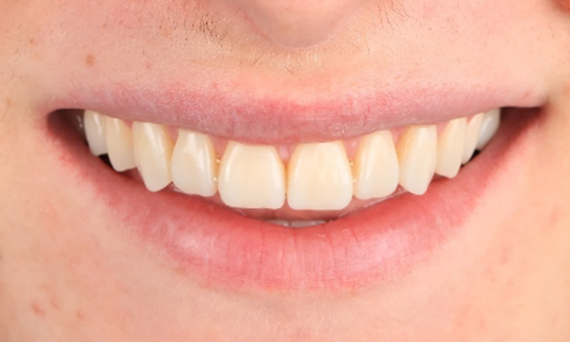

Before: Clinical Situation pre-op. Trauma of upper central incisors

After: Adhesively bonded restorations.